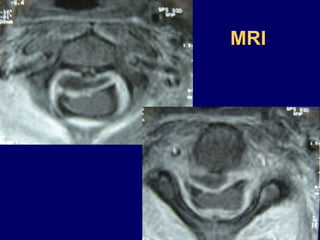

MRI

Anterior procedure

Vertebrectomy - PUS evacuation + Stabilization